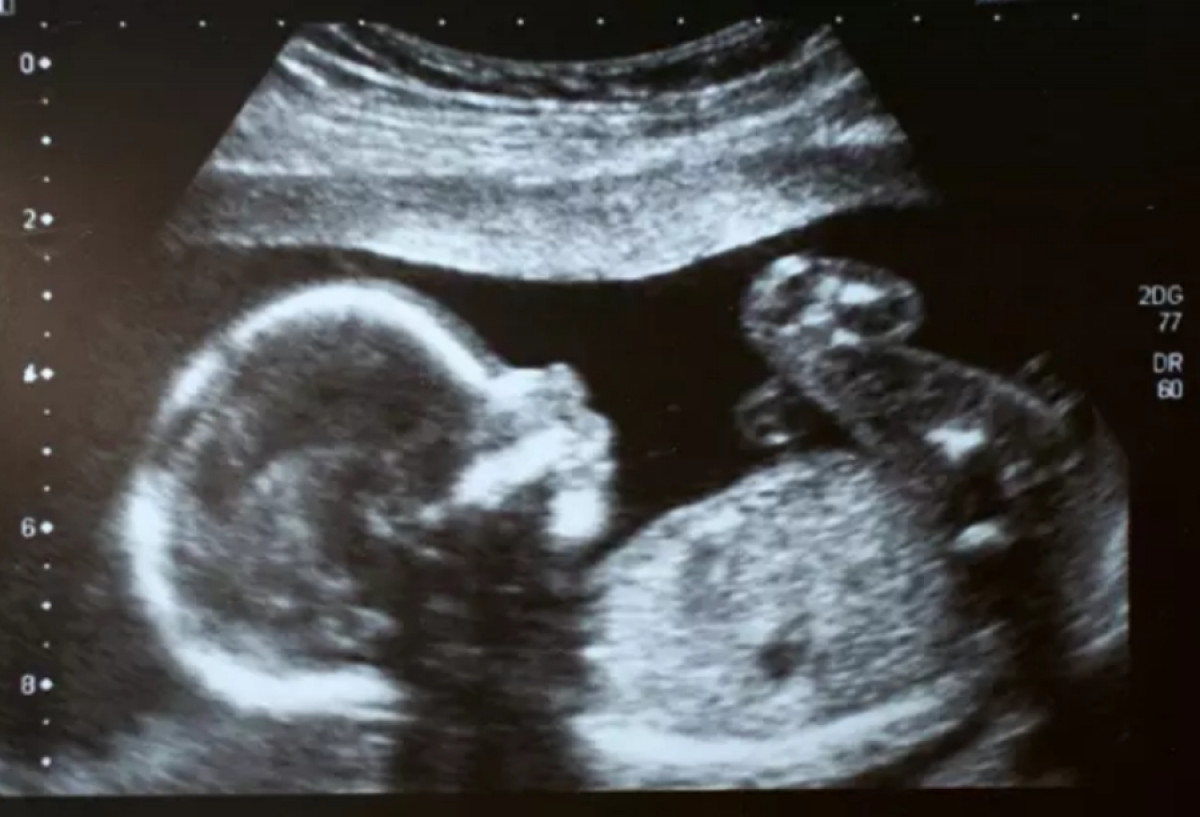

Una ecografía. Foto: iStock